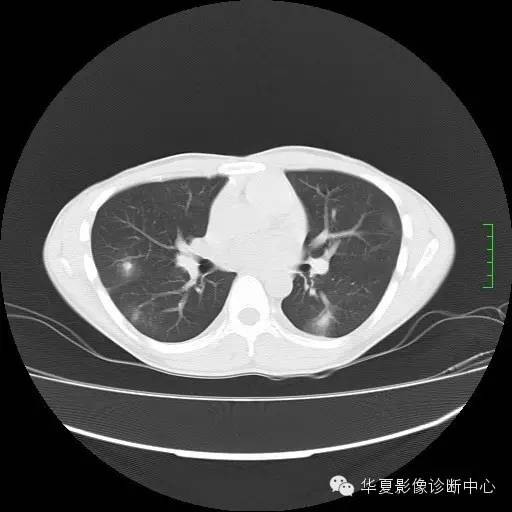

CT平扫:两肺外围多发结节伴晕征